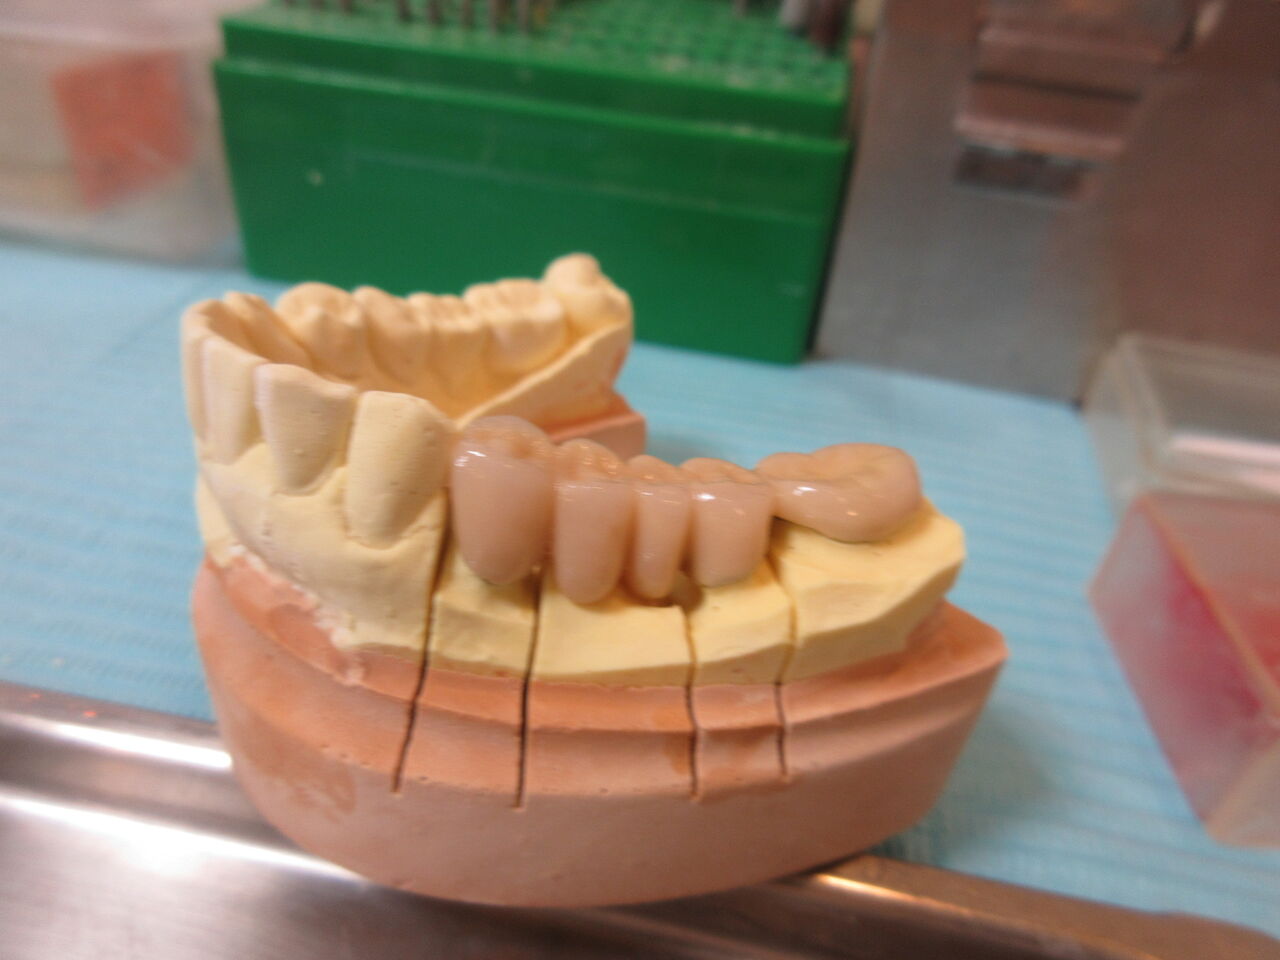

メタルボンドブリッジ

最近はメタルボンド(内面が金属)が少なくなりましたが、以前の自費治療はメインでした。

このようなブリッジを装着。